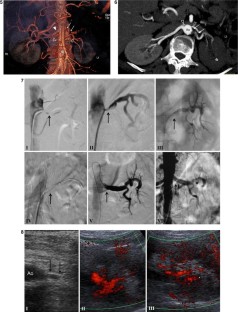

Fig. 5–8